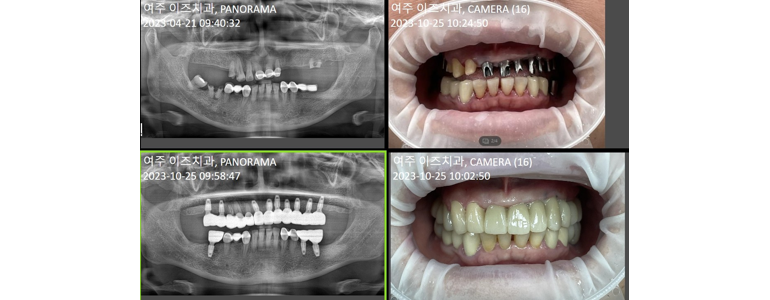

여주이즈치과의원은 경기 여주시 세종로에 위치하며, 첨단 장비와 전문의의 진료로 신속하고 정확한 치료를 제공합니다. 특히 임플란트 및 매랑니 발치 로 유명한 병원으로, 많은 환자들이 믿고 찾고 있습니다.